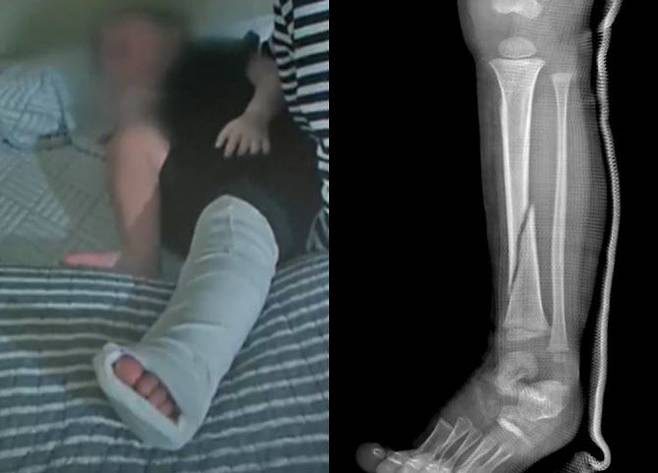

C씨가 도착한 뒤에야 B군은 인근 병원으로 이송돼 골절 진단을 받았고, 깁스를 한 채 어린이집으로 다시 돌아왔다.

D씨는 아이의 상태를 더 정확히 확인하기 위해 상급 병원에서 추가 진단을 받았고 진단명은 '좌측 경골 몸통의 기타 골절, 폐쇄성’이었다.

왼쪽 정강이의 굵은 뼈가 부러져 발목 쪽으로 밀려 내려갔고 전치 14주의 치료가 필요했다.

D씨는 "의사가 '어떤 힘으로 눌렀기에 이렇게 큰 뼈가 부러지냐'고 물었다"며 "성인이 된 후에도 절뚝거릴 수 있다는 말을 듣고 하늘이 무너지는 기분이었다"고 호소했다.